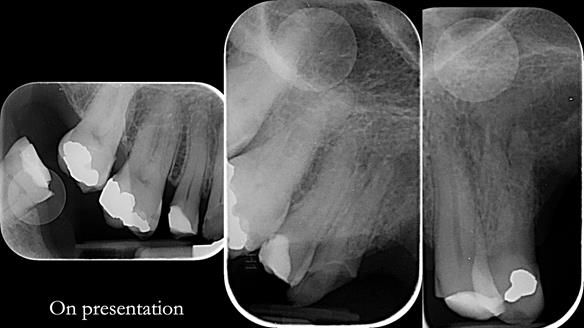

Keith’s case was one of the most challenging and rewarding cases I’ve treated this year. This 64 year old man presented with ill-fitting acrylic partial dentures that lacked stability, retention, and aesthetics. They constantly broke. He had lost the upper front teeth in a road traffic accident in his early 20s. The unopposed teeth had erupted, taking up space. After careful planning, we made a durable, metal-based upper partial denture/splint to address his dental concerns. He loved the outcome.

2. Onlay preparations: Composite onlays were fitted for his upper left premolars to repair these teeth and support the new denture.